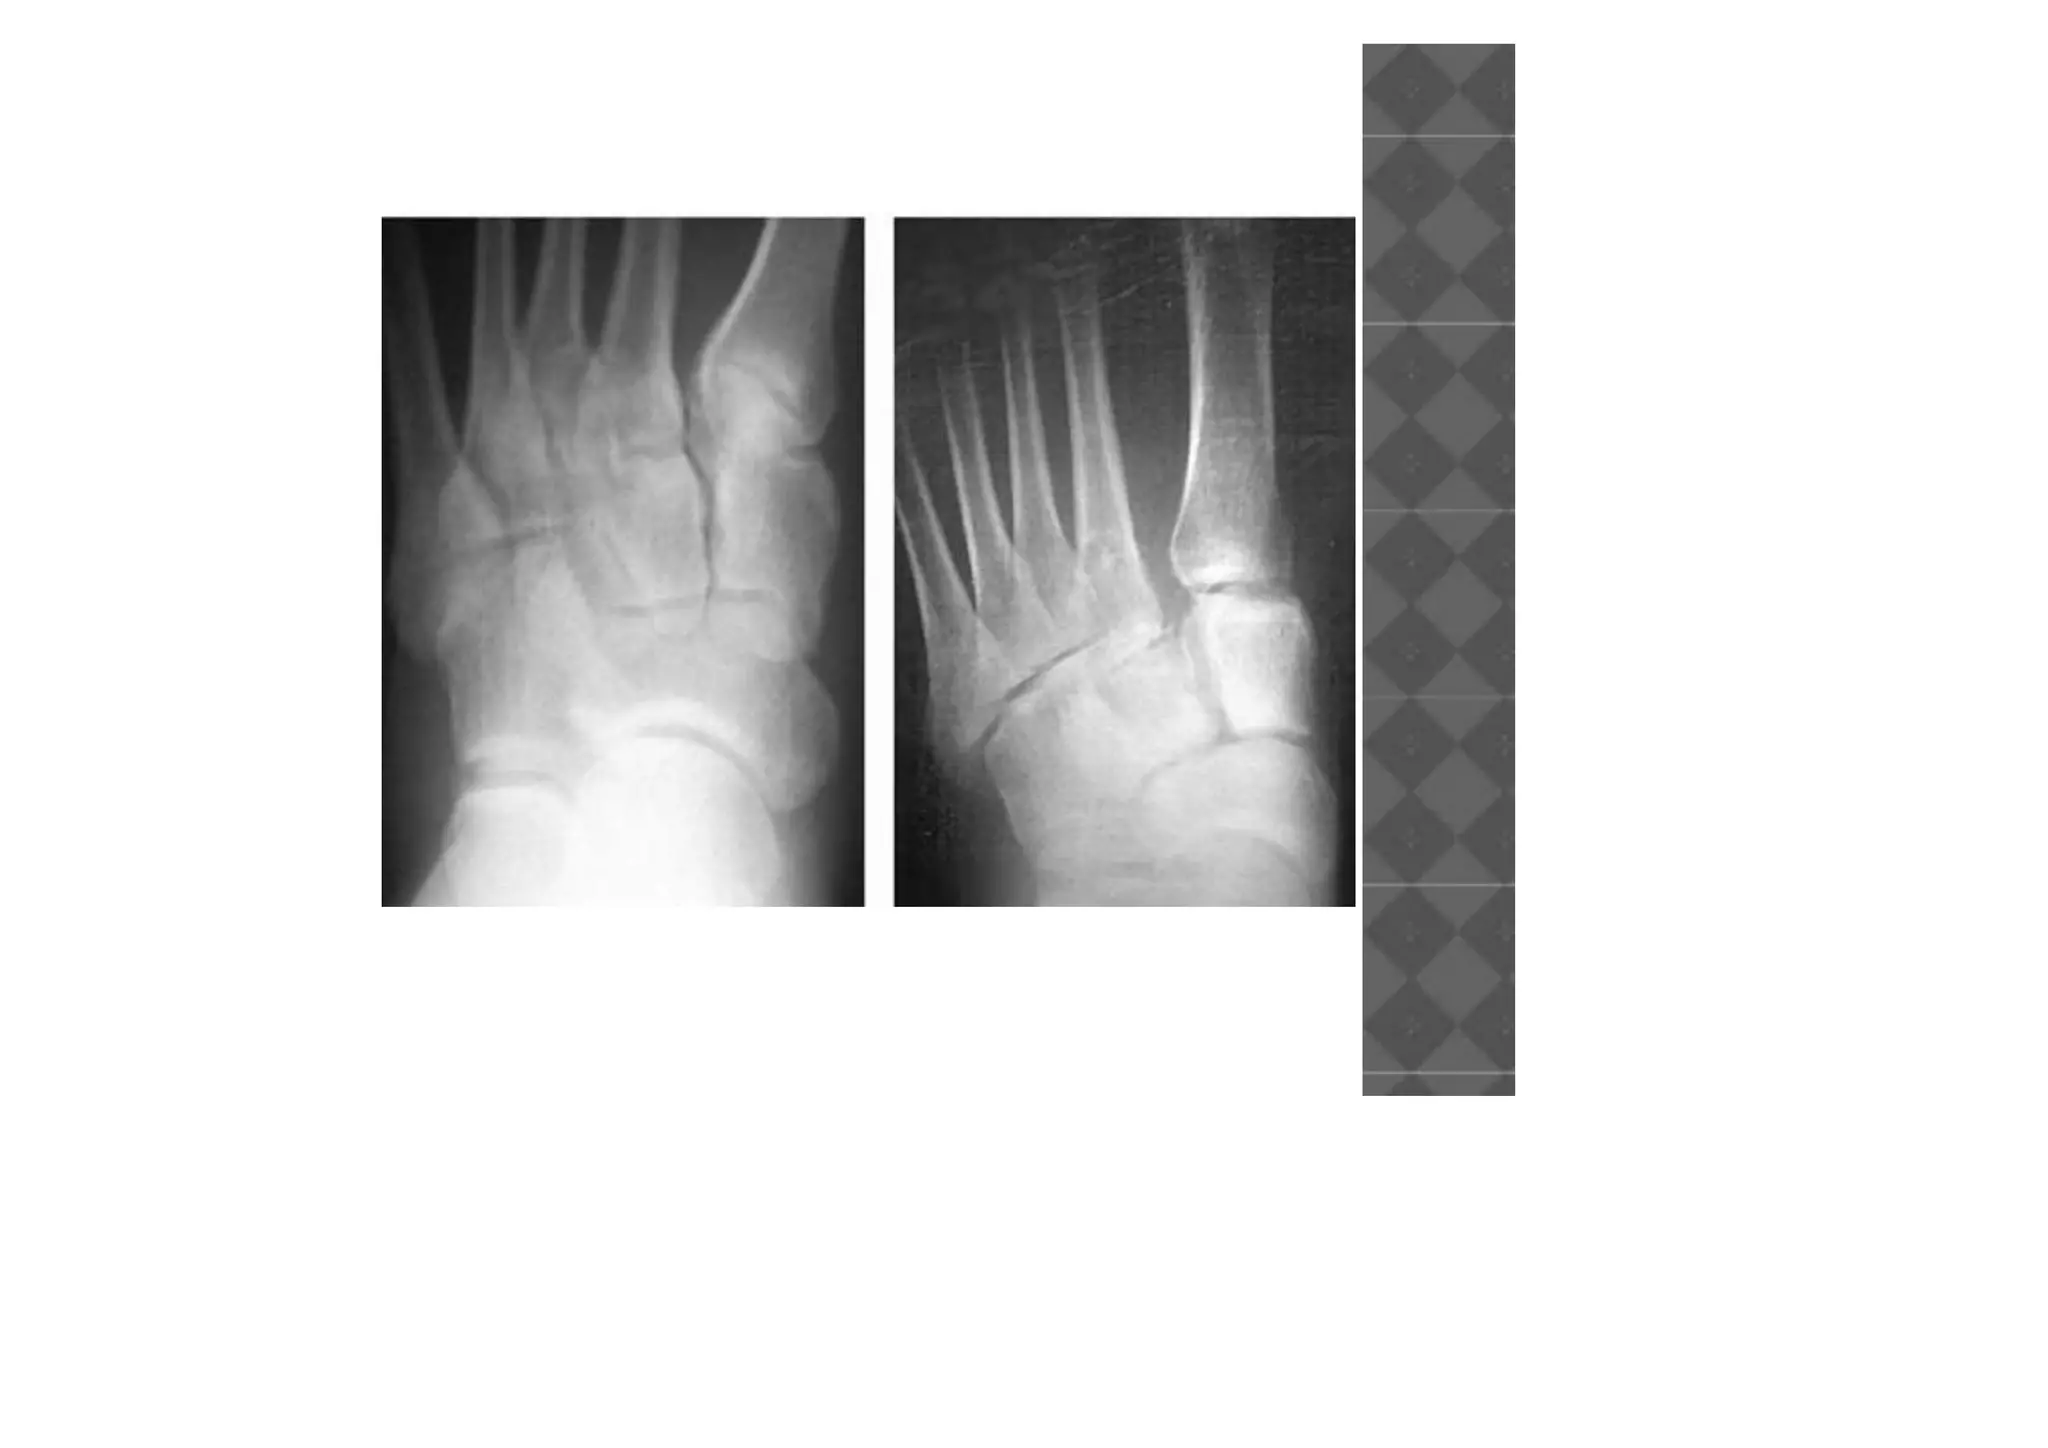

RADIOGRAPHIC EVALUATION

• The medial border of the second metatarsal

should be colinear with the medial border of

the middle cuneiform on the AP view

• The medial border of the fourth metatarsal

the cuboid on the oblique view

• Dorsal displacement of the metatarsals on

the lateral view is indicative of ligamentous

compromise.

• Fleck fractures around the base of the

second metatarsal are indicative of

disruption of Lisfranc joint.

RADIOGRAPHIC EVALUATION • Themedial border of the second metatarsal should be colinear with the medial border of the middle cuneiform on the AP view • The medial border of the fourth metatarsal should be colinear with the medial border of the cuboid on the oblique view

• Dorsal displacementof the metatarsals on the lateral view is indicative of ligamentous compromise. • Fleck fractures around the base of the second metatarsal are indicative of disruption of Lisfranc joint.

• #14 The medial border of the second metatarsal should be colinear with the medial border of the middle cuneiform on the AP view The medial border of the fourth metatarsal should be colinear with the medial border of the cuboid on the oblique view

• #15 The medial border of the second metatarsal should be colinear with the medial border of the middle cuneiform on the AP view The medial border of the fourth metatarsal should be colinear with the medial border of the cuboid on the oblique view